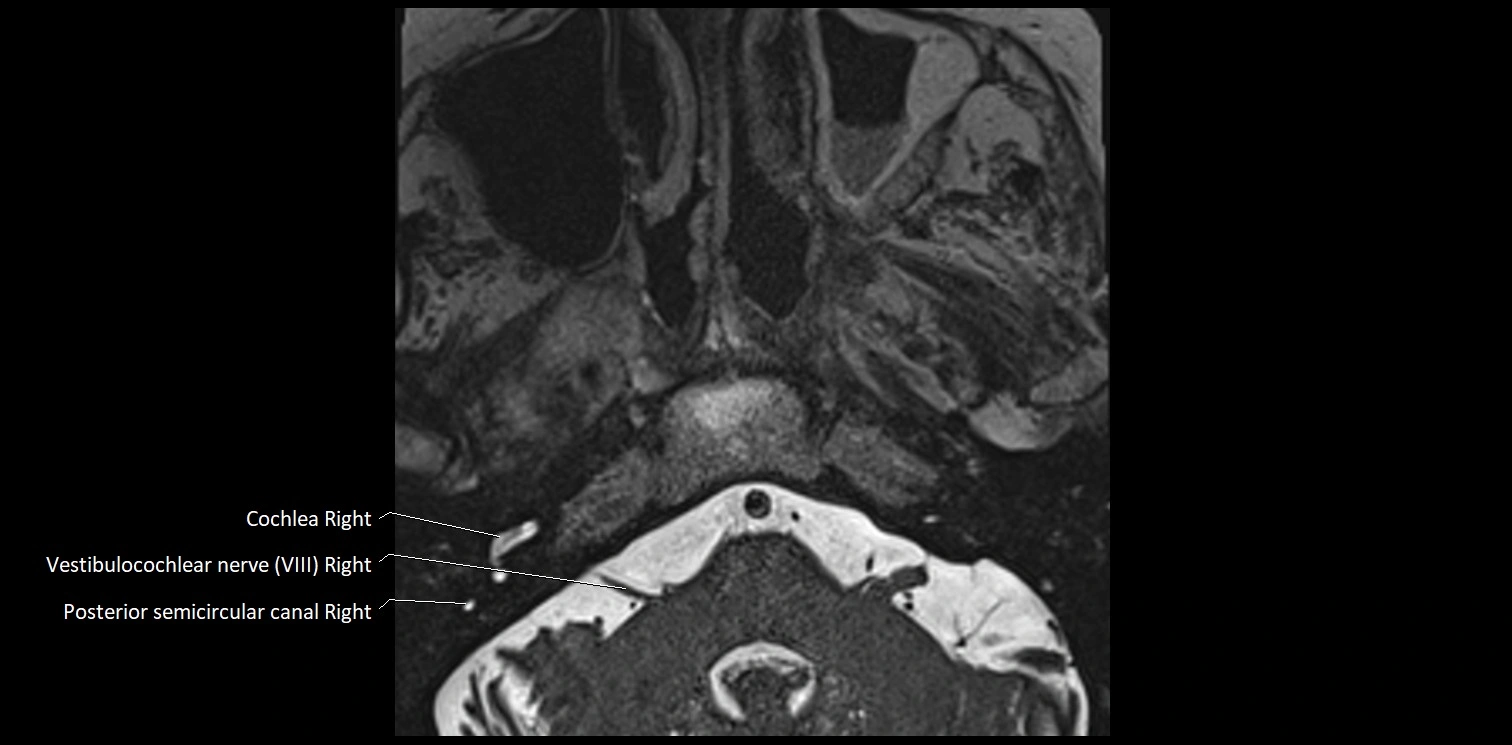

MRI Appearance

• The abducens nerve is a small, thin, linear structure

• Best visualized on high-resolution T2-weighted 3D MRI sequences (e.g., FIESTA or CISS)

• Seen as a hypointense (dark) line running from the brainstem at the pontomedullary junction, traversing the prepontine cistern, and entering Dorello’s canal under the petrosphenoidal ligament, then into the cavernous sinus, and finally the orbit

• May be challenging to visualize in standard MRI due to its small size

• Pathology may be inferred by absence, displacement, or enhancement of the nerve